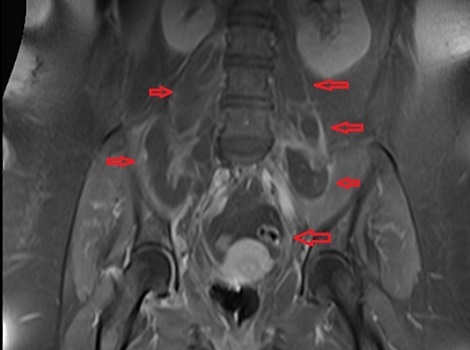

Στις εικόνες της μαγνητικής διακρίνονται τα διάφορα αποστήματα (κόκκινα βέλη) στους μύες (λαγνοψωίτες, απιοειδείς και δεξιό γλουτιαίο).

Το απόστημα του δεξιού λαγονοψωίτη καταλάμβανε ολόκληρη την έκταση του μυός. Τέλος, σημαντικό νέο εύρημα ήταν η παρουσία επισκληρίδιου εμπυήματος το οποίο κρίθηκε ότι δεν χρειάζεται χειρουργείο.